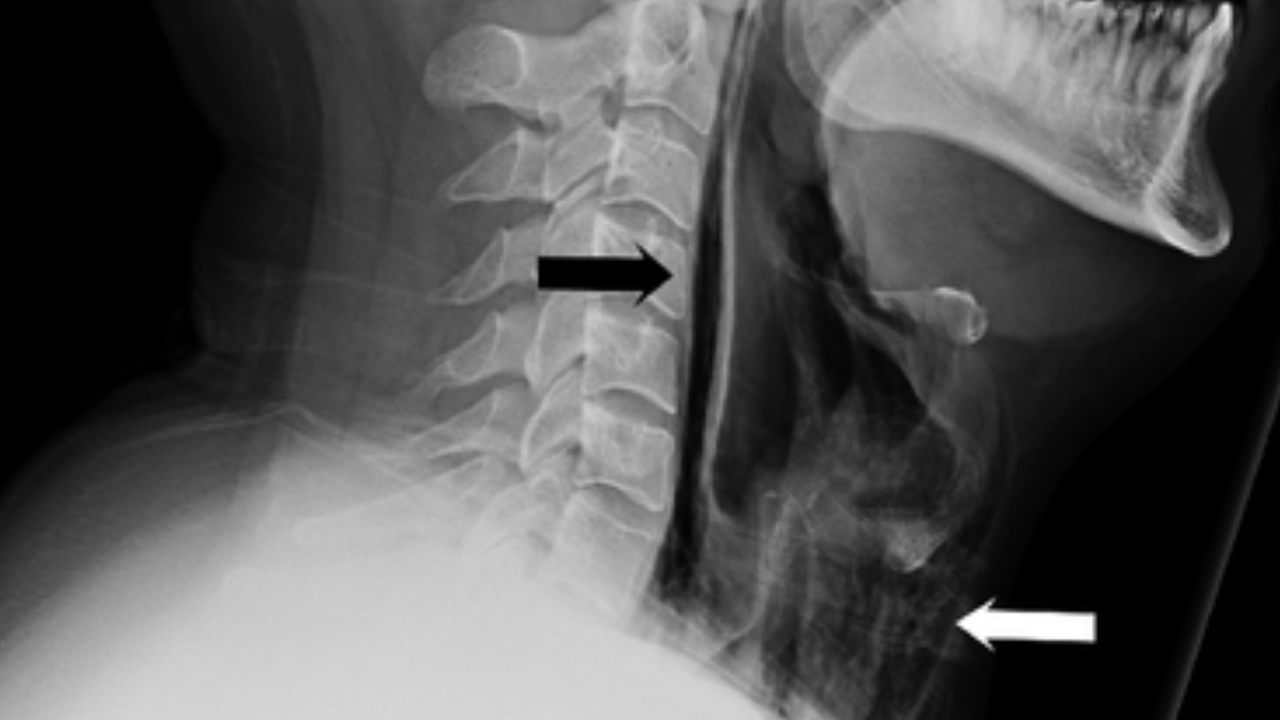

Scans confirmed the problem. The tests showed actual streaks of air in the retropharyngeal region and extensive surgical emphysema in the neck anterior to the trachea. In other words, by trying to hold in his sneeze, he actually blew a small hole in his throat.